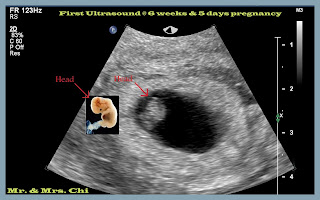

懷孕初期 First Trimester 3/28 - 6/12

懷孕現在走到後期,再來回憶初期的事情,覺得已經是很久以前的事情。還好我還有保留一些當時的文字,來提醒我那時候的心情。雖然說對生孩子一直都是抱持著順其自然的態度,但是順了五年卻一直都沒有自然發生,不免也是會懷疑自己是不是有什麼問題。我們終於在2011年底開始看醫生跟積極的量體溫+照表操課,檢查結果兩人都相當健康,什麼原因造成五年沒懷孕,大概只能擲茭問神,總之,不是不到,只是時候未到。